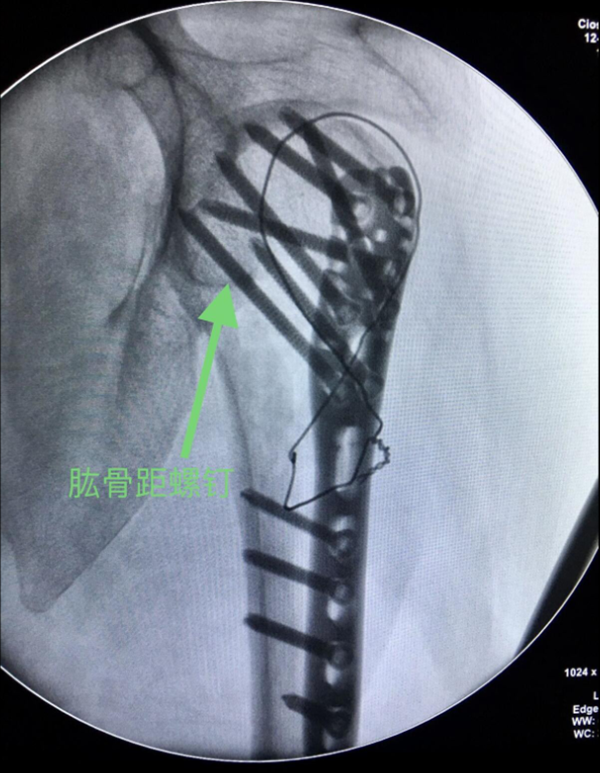

(5)注意肱骨距内侧支撑复位肱骨距,如果内侧皮质支撑结构破坏广泛,可采用髓腔内结构性植骨以重建内侧支撑。如内侧皮质结构尚完整,但出现了内侧的阴性支撑,则需要使用肱骨距螺钉斜跨干骺端与后内侧皮质以行支撑。

图13 肱骨距螺钉固定

十、手术注意事项

2、注意肱骨距的修复与重建,肱骨头骨折块复位不佳存在内翻移位或肱骨距骨缺损,肱骨没有很好地重建内侧的支撑,导致继发性的复位丢失或内固定断裂。可以采用髓腔内结构性植骨以重建内侧支撑。如果内侧皮质结构尚完整,可以使用肱骨距螺钉斜跨干端与后内侧皮质以行支撑。